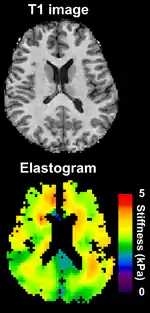

Because elastography does not have the same limitations as manual palpation, it is being investigated in some areas for which there is no history of diagnosis with manual palpation. For example, magnetic resonance elastography is capable of assessing the stiffness of the brain, and there is a growing body of scientific literature on elastography in healthy and diseased brains.

Magnetic resonance elastography (MRE)[25] was introduced in the mid-1990s, and multiple clinical applications have been investigated. In MRE, a mechanical vibrator is used on the surface of the patient's body; this creates shear waves that travel into the patient's deeper tissues. An imaging acquisition sequence that measures the velocity of the waves is used, and this is used to infer the tissue's stiffness (the shear modulus).[26][27] The result of an MRE scan is a quantitative 3-D map of the tissue stiffness, as well as a conventional 3-D MRI image.

One strength of MRE is the resulting 3D elasticity map, which can cover an entire organ.[2] Because MRI is not limited by air or bone, it can access some tissues ultrasound cannot, notably the brain. It also has the advantage of being more uniform across operators and less dependent on operator skill than most methods of ultrasound elastography.